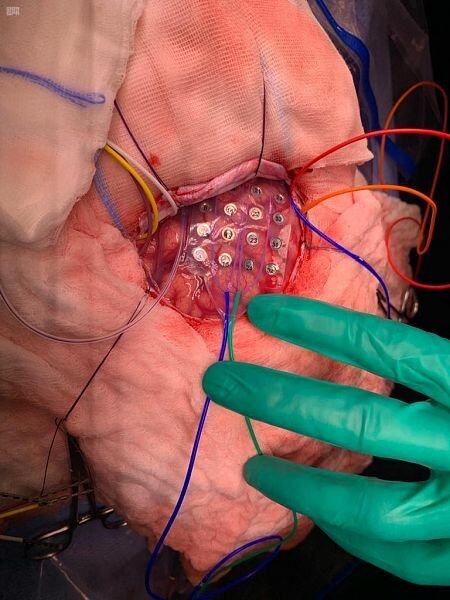

وأوضحت إدارة المستشفى أن المريض طفل يبلغ من العمر 11 عاماً يعاني من الصرع، وقد تمكن الفريق الطبي من تحديد بؤرة الصرع بالرنين المغناطيسي وتخطيط الدماغ السطحي والاجتياحي، حيث تبين أن بؤرة الصرع قريبة من مركز الكلام والحركة، ولمزيد من تحديد المراكز المهمة فقد أُوقظ المريض أثناء العملية لفترة مؤقتة لاستئصال بؤرة الصرع، لتلافي التلف للمراكز الحيوية في الدماغ.